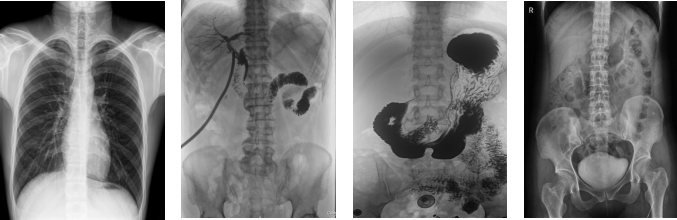

PLD8000C数字胃肠DR机全面突破传统X射线摄影透视理念,成像部件采用新型动态平板探测器,轻松解决数字摄影、数字透视、数字造影等功能,并使数字透视获得超大尺寸和清晰的图像效果。满足放射科、体检中心、影像中心、内科、妇科、外科、急诊科、骨科、创伤科、消化科等科室的各种临床检查需求。如果您想采购这款数字胃肠DR机,欢迎咨询400-025-6366。